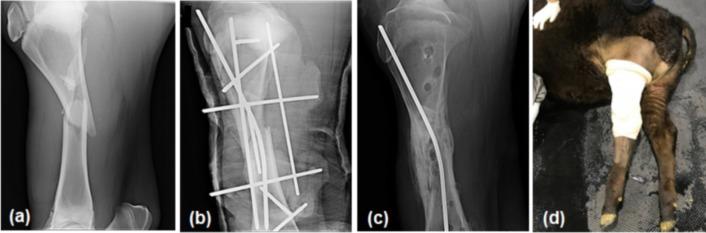

The aim of this study was to examine the treatment outcomes of tibial fracture using different configurations of transfixation pinning and casting (TPC) in eight cattle. After pins were inserted to stabilize the fracture site, cast material was placed from the level of the stifle to the hoof (full TPC) in six cases and from the stifle to the proximal metatarsus (partial TPC) in two cases. Five cattle (three full TPC and two partial TPC cases) underwent TPC removal 36-86 days after surgery and resumed productivity. The other three cattle which underwent full TPC suffered from irreversible orthopedic complications within 5 weeks of surgery, while a prolonged healing process was observed in the partial TPC cases. Although TPC is an effective method for treating bovine tibial fracture, full TPC may result in a guarded prognosis in some cattle. However, partial TPC can delay healing. Surgeons should choose the optimal TPC configuration while considering the various factors that affect the healing process.

本研究的目的是检查八头牛采用不同构型的贯穿针固定和石膏固定(TPC)治疗胫骨骨折的效果。在插入钢针以稳定骨折部位后,六例从膝关节水平至蹄部放置石膏材料(全TPC),两例从膝关节至跖骨近端(部分TPC)。五头牛(三例全TPC和两例部分TPC)在术后36 - 86天进行了TPC移除并恢复了生产性能。另外三头接受全TPC的牛在术后5周内出现了不可逆的骨科并发症,而部分TPC病例观察到愈合过程延长。虽然TPC是治疗牛胫骨骨折的有效方法,但全TPC在某些牛中可能导致预后不佳。然而,部分TPC会延迟愈合。外科医生在考虑影响愈合过程的各种因素时应选择最佳的TPC构型。